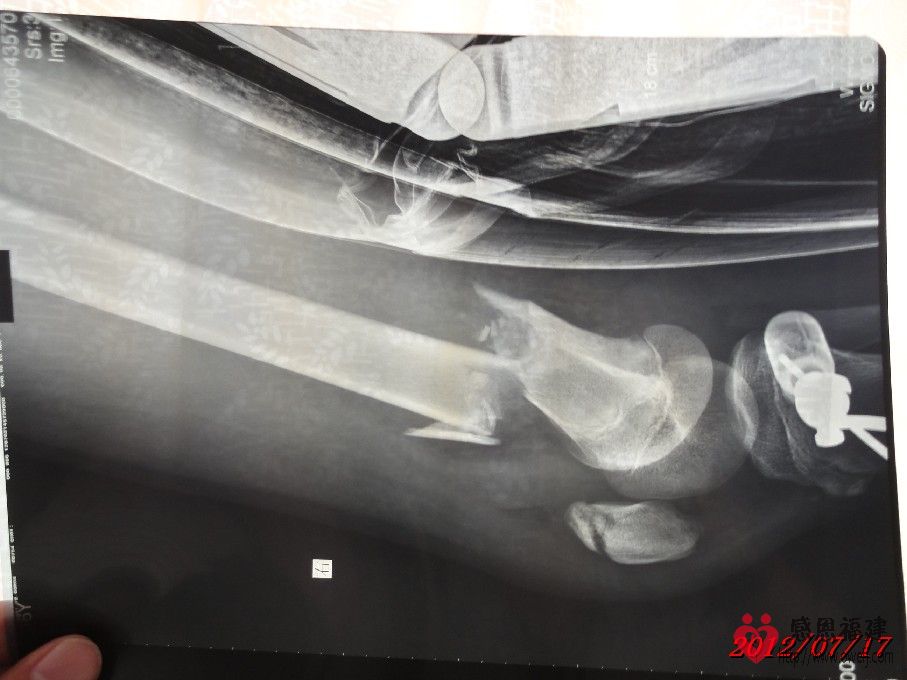

1、事故情况:2012年7月1日14:30左右,智在同学骑邻居的无牌照XGJ125摩托车载着两个同学在北洋小学附近的123县道与停在路旁的无牌照货车发生碰撞(据孩子介绍货车基本占了半边马路,当时对面刚好有车驶来,智在为了避免和对面车发生碰撞往右避让,结果撞上了停在路旁的货车的左后角),导致摩托车撞坏、智在右大腿骨折和另外一位同学大腿骨折。

2、住院情况:事故发生后家人将智在送往闽清县医院治疗,医院同意住院并可安排第二天手术;但智在是一家四口中唯一没有残疾的(由于残疾的父亲在医院照顾智在,哑巴的母亲精神不好还时常跑回老家又不会照顾人,导致眼睛残疾的小弟弟几天没吃上两顿饭),家人和亲戚为了智在治疗后不留下后遗症,最后决定送往福州市第二医院治疗,并于当晚存了2,000元住院费并办好住院手续。但由于家境贫寒,智在的父亲和亲戚到处借债(有的500,有的1,000……),好不容易东拼西凑才筹集到手术费用(现在已经累计存入医院38,000元),手术于7月11日进行,效果还比较理想,但出院时间待定。